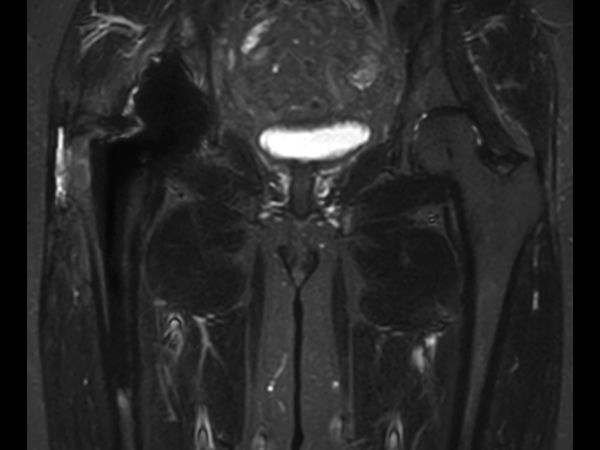

Hip imaging with metal implant

Used Solution

**Only for use with MR Safe or MR Conditional Implants by strictly following the Instructions for Use.